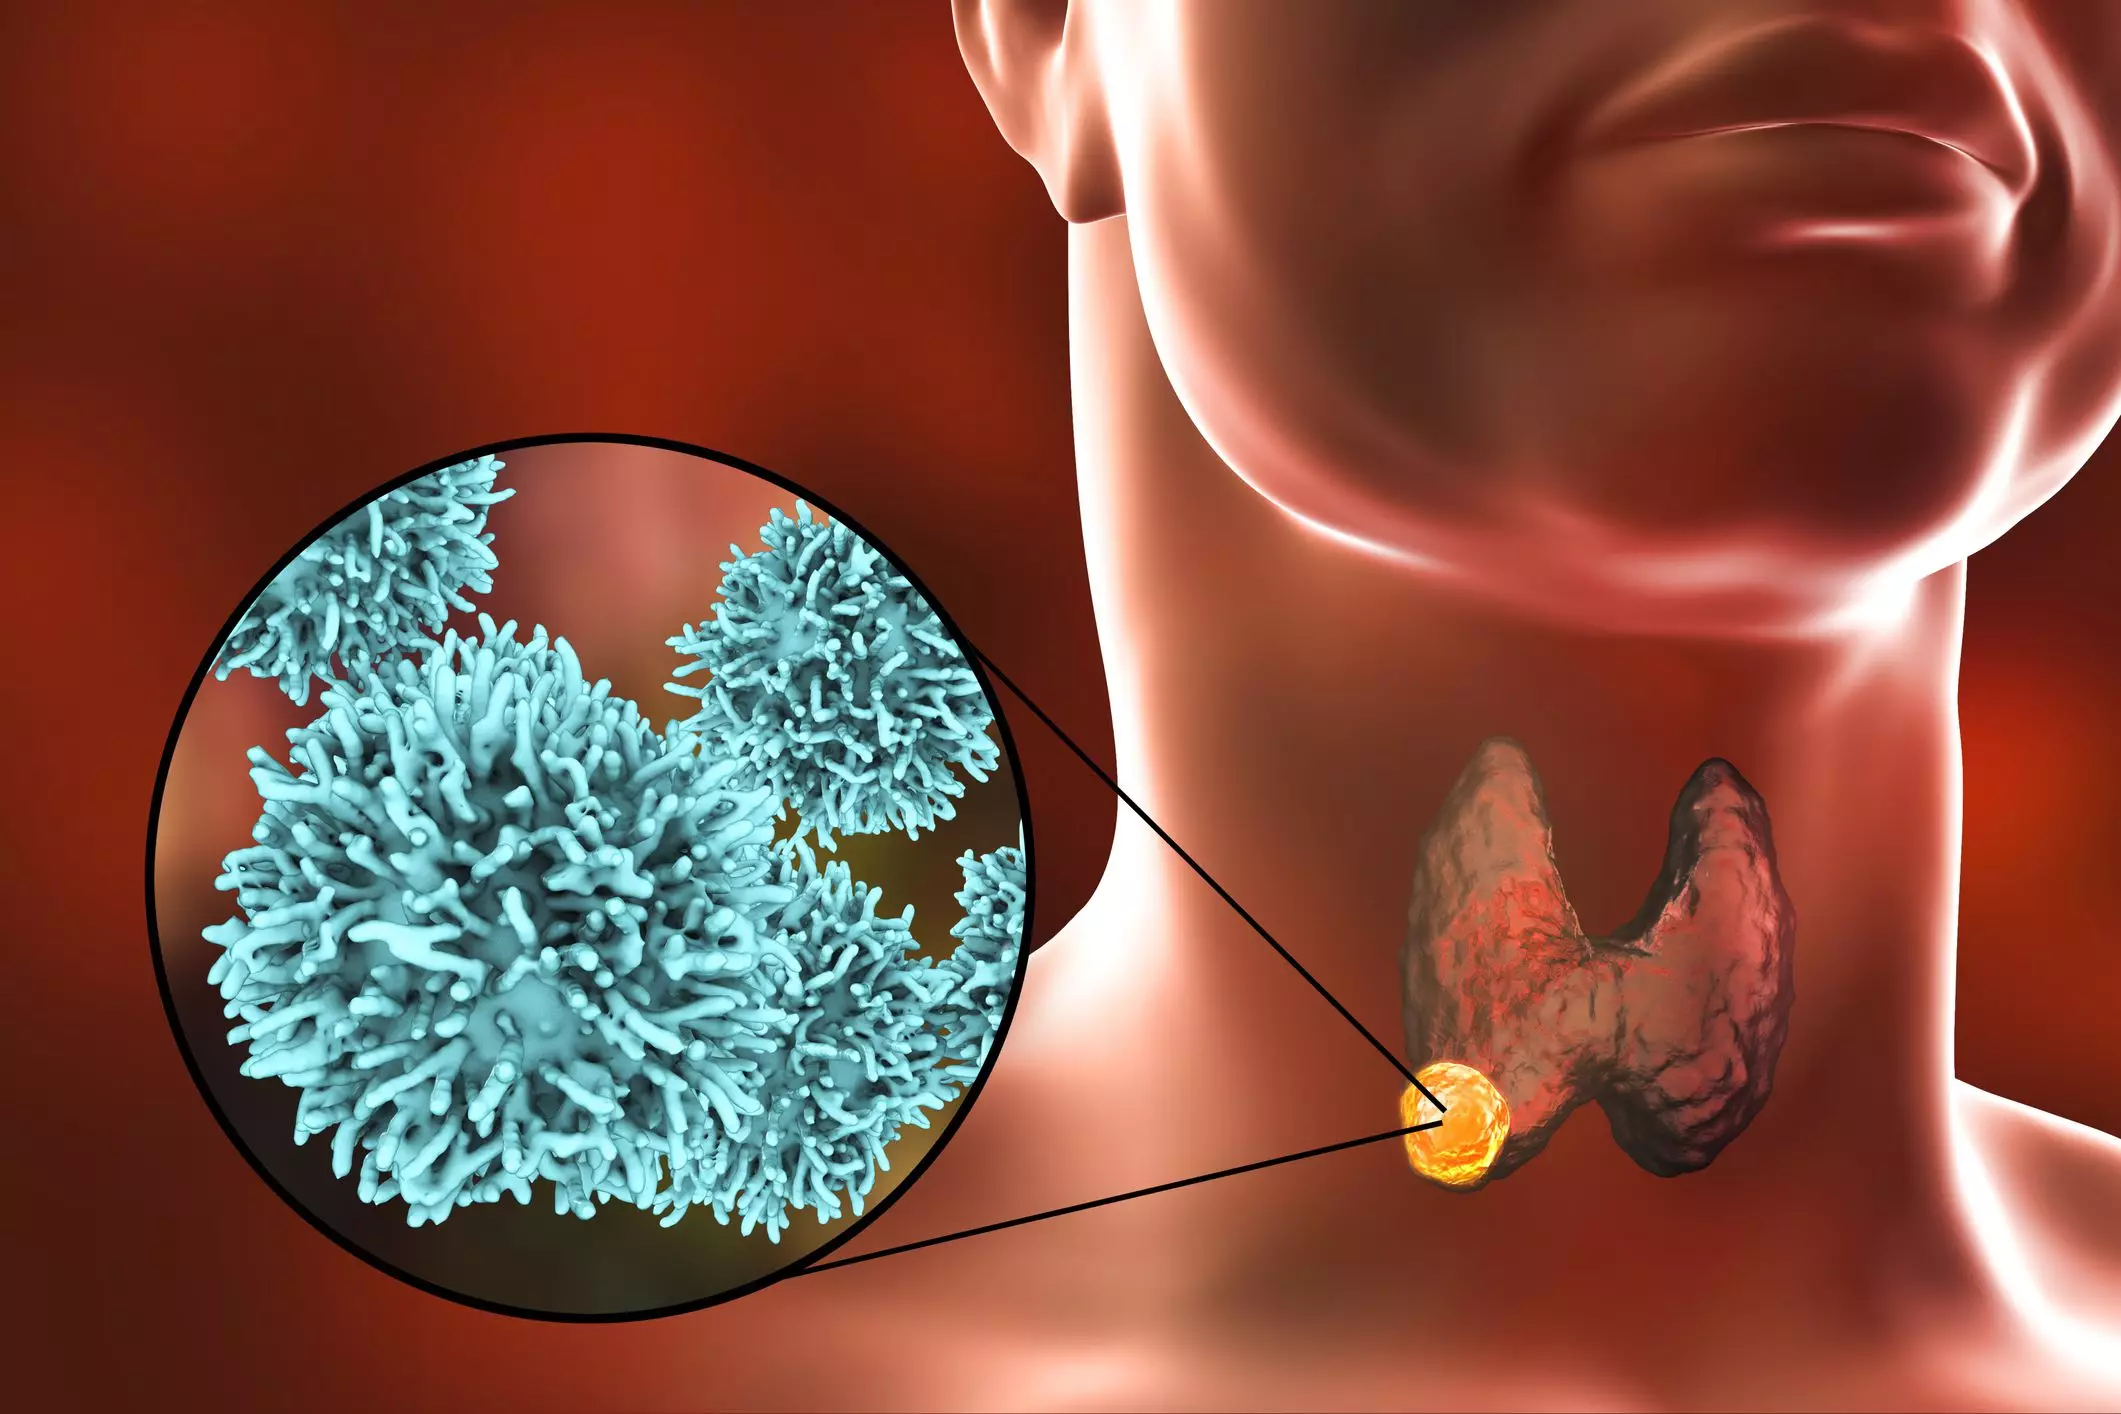

Раковая шишка – это заболевание, которое поражает кожу и слизистые оболочки. Она может возникнуть в различных частях тела и иметь различные внешние проявления. В данной статье мы представляем вам многочисленные фотографии раковых шишек, чтобы вы могли узнать, как они выглядят.

Раковые шишки могут возникать не только на лице, но и на других частях тела. На фотографиях вы можете увидеть примеры раковых шишек на шее, руках, ногах и туловище. Обратите внимание на различные формы и размеры раковых шишек, а также на их внешний вид.